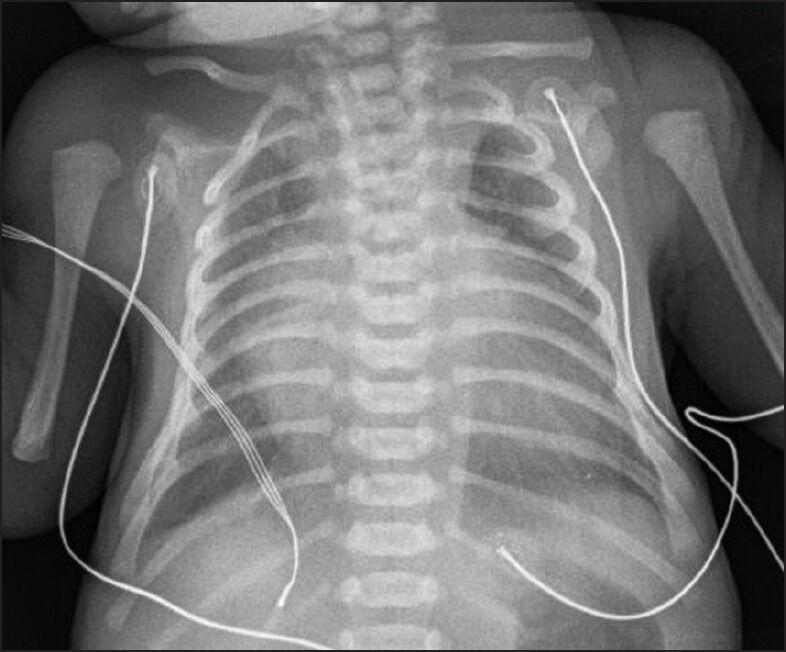

This is a case report of a patient with Trisomy 21 with Ebstein anomaly, a ventricular septal defect, and acquired pulmonary vein stenosis; a rare combination, diagnosed during a routine neonatal examination.

这是一份关于一名患有21三体综合征合并埃布斯坦畸形、室间隔缺损和后天性肺静脉狭窄患者的病例报告,这种罕见的组合在常规新生儿检查中被诊断出来。